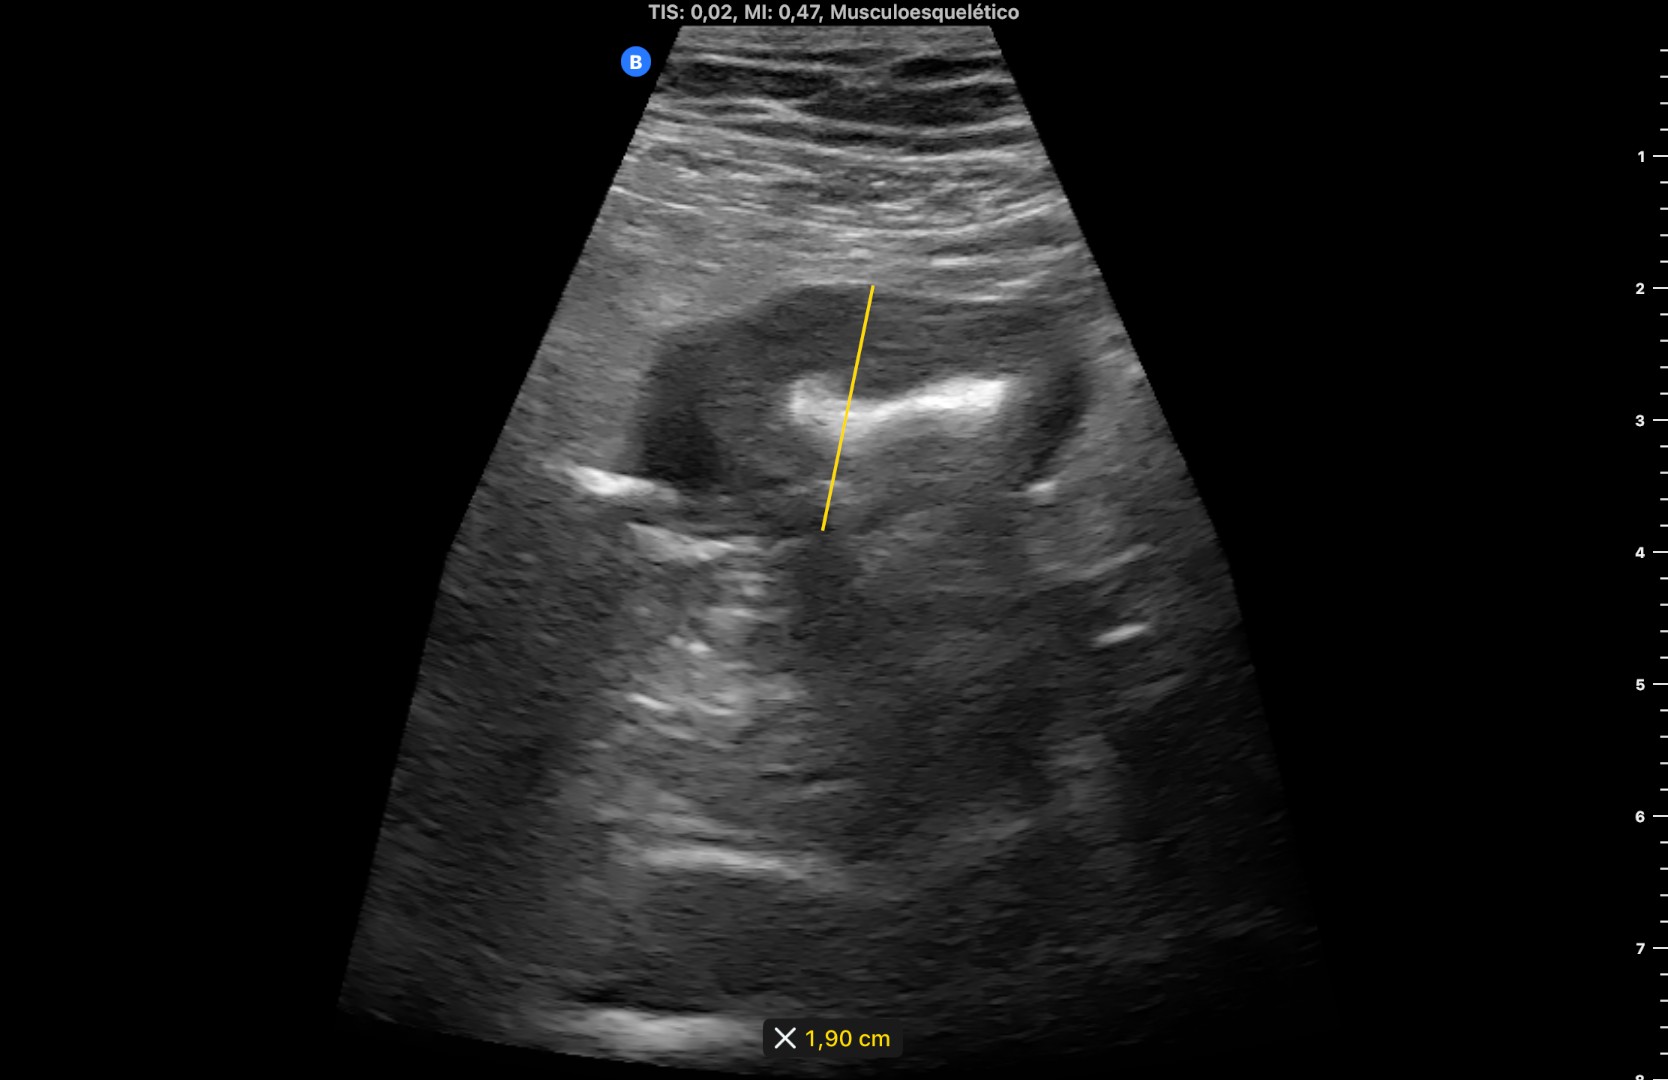

Hallazgos ecográficos: Se objetiva imagen de tubo digestivo a nivel sigmoideo, con engrosamiento de pared que alcanza los 1,9 cm de diámetro (fotos 1 y 2) y que sugiere diverticulitis aguda (hay vídeo).